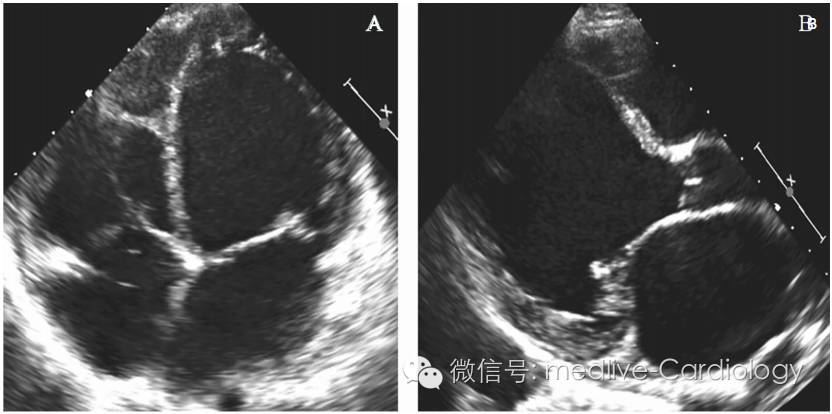

最初考虑为冠脉血管病变引起心衰,遂行冠脉造影术,结果提示前降支存在30%狭窄,其余冠脉血管管腔轻度不规则改变。甲状腺功能正常。给予华法林、琥珀酸美托洛尔(控制心室率和改善心肌重构)、赖诺普利治疗。12周后,MK因心棒、呼吸困难再次住院,当时静息心率为130次/分,收缩压为70mmHg。体格检查:颈静脉压为16cmH20(约为1568Pa),心尖冲动向左侧移位,奔马律,肺部听诊可闻及湿性啰音,双下肢水肿。复查超声心动图LVEF 10%~15%(图2)。加用更大剂量利尿剂,应用地高辛以改善心室率控制效果,增强心肌收缩 力。在优化药物治疗心衰基础上,植入双腔ICD。

图2 超声心动图:心动过速介导的心肌病。(A)心尖四腔切面;(B)胸骨旁长轴切面。

在以后的复诊中,MK症状明显好转,但仍有轻度呼吸困难和持续的心悸症状。已行冠脉造影检查排除因心肌缺血引起的心衰,故AF为患者出现心衰的病因。在不应用美托洛尔和地高辛的情况下,静息心率为105次/分。体格检查:颈静脉压5cmH2O(约490Pa),第一心音强弱不等,各瓣膜听诊区未闻及杂音,心尖冲动正常。肺部听诊未闻及湿啰音,腹软无膨胀,双下肢无水肿,末端动脉搏动存在,四肢温暖。心电图提示心房颤动、非特异性T波异常改变。ICD程控过程中证实有持续性AF伴快心室率,心室率常在180次/分以上,现在排除了心肌缺血、内分泌、心脏毒性物质的影响,考虑MK为心动过速性心肌病。